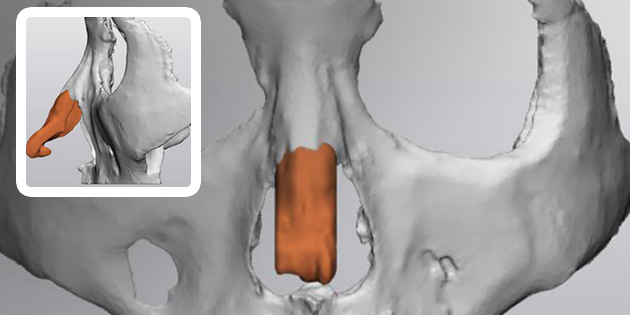

This is 1:1 customized rhinoplasty that allows you to create the most suitable implant for your nose by using 3D printer to create the patient’s skeleton, cartilage, skin tissue, and muscle with data obtained from 3D-ct images.

Because it is possible to manufacture a customized implant that fits perfectly to the nasal bone, it is safe and there is little worry about reoperation as it significantly reduces side effects such as bending, silicone seepage, and lifting.

4Custom Nose Implant

A custom-designed, custom-made nose implant for patients is made with a 3D printer.

How is it different from general rhinoplasty?

Satisfaction is different. Ordinary implants have a flat bottom, so it is difficult to design a delicate implant depending on the shape of the patient’s nose. I’m on the side.

Are there any side effects?

Yes. There are really few side effects. If an implant is made during the surgical procedure using popular silicone, the operation time will be longer and there may be more swelling. On the other hand, 3D customized rhinoplasty reduces the operation time and prevents the implant from dislodging because the implant is made in advance and used immediately during surgery, resulting in significantly fewer side effects.